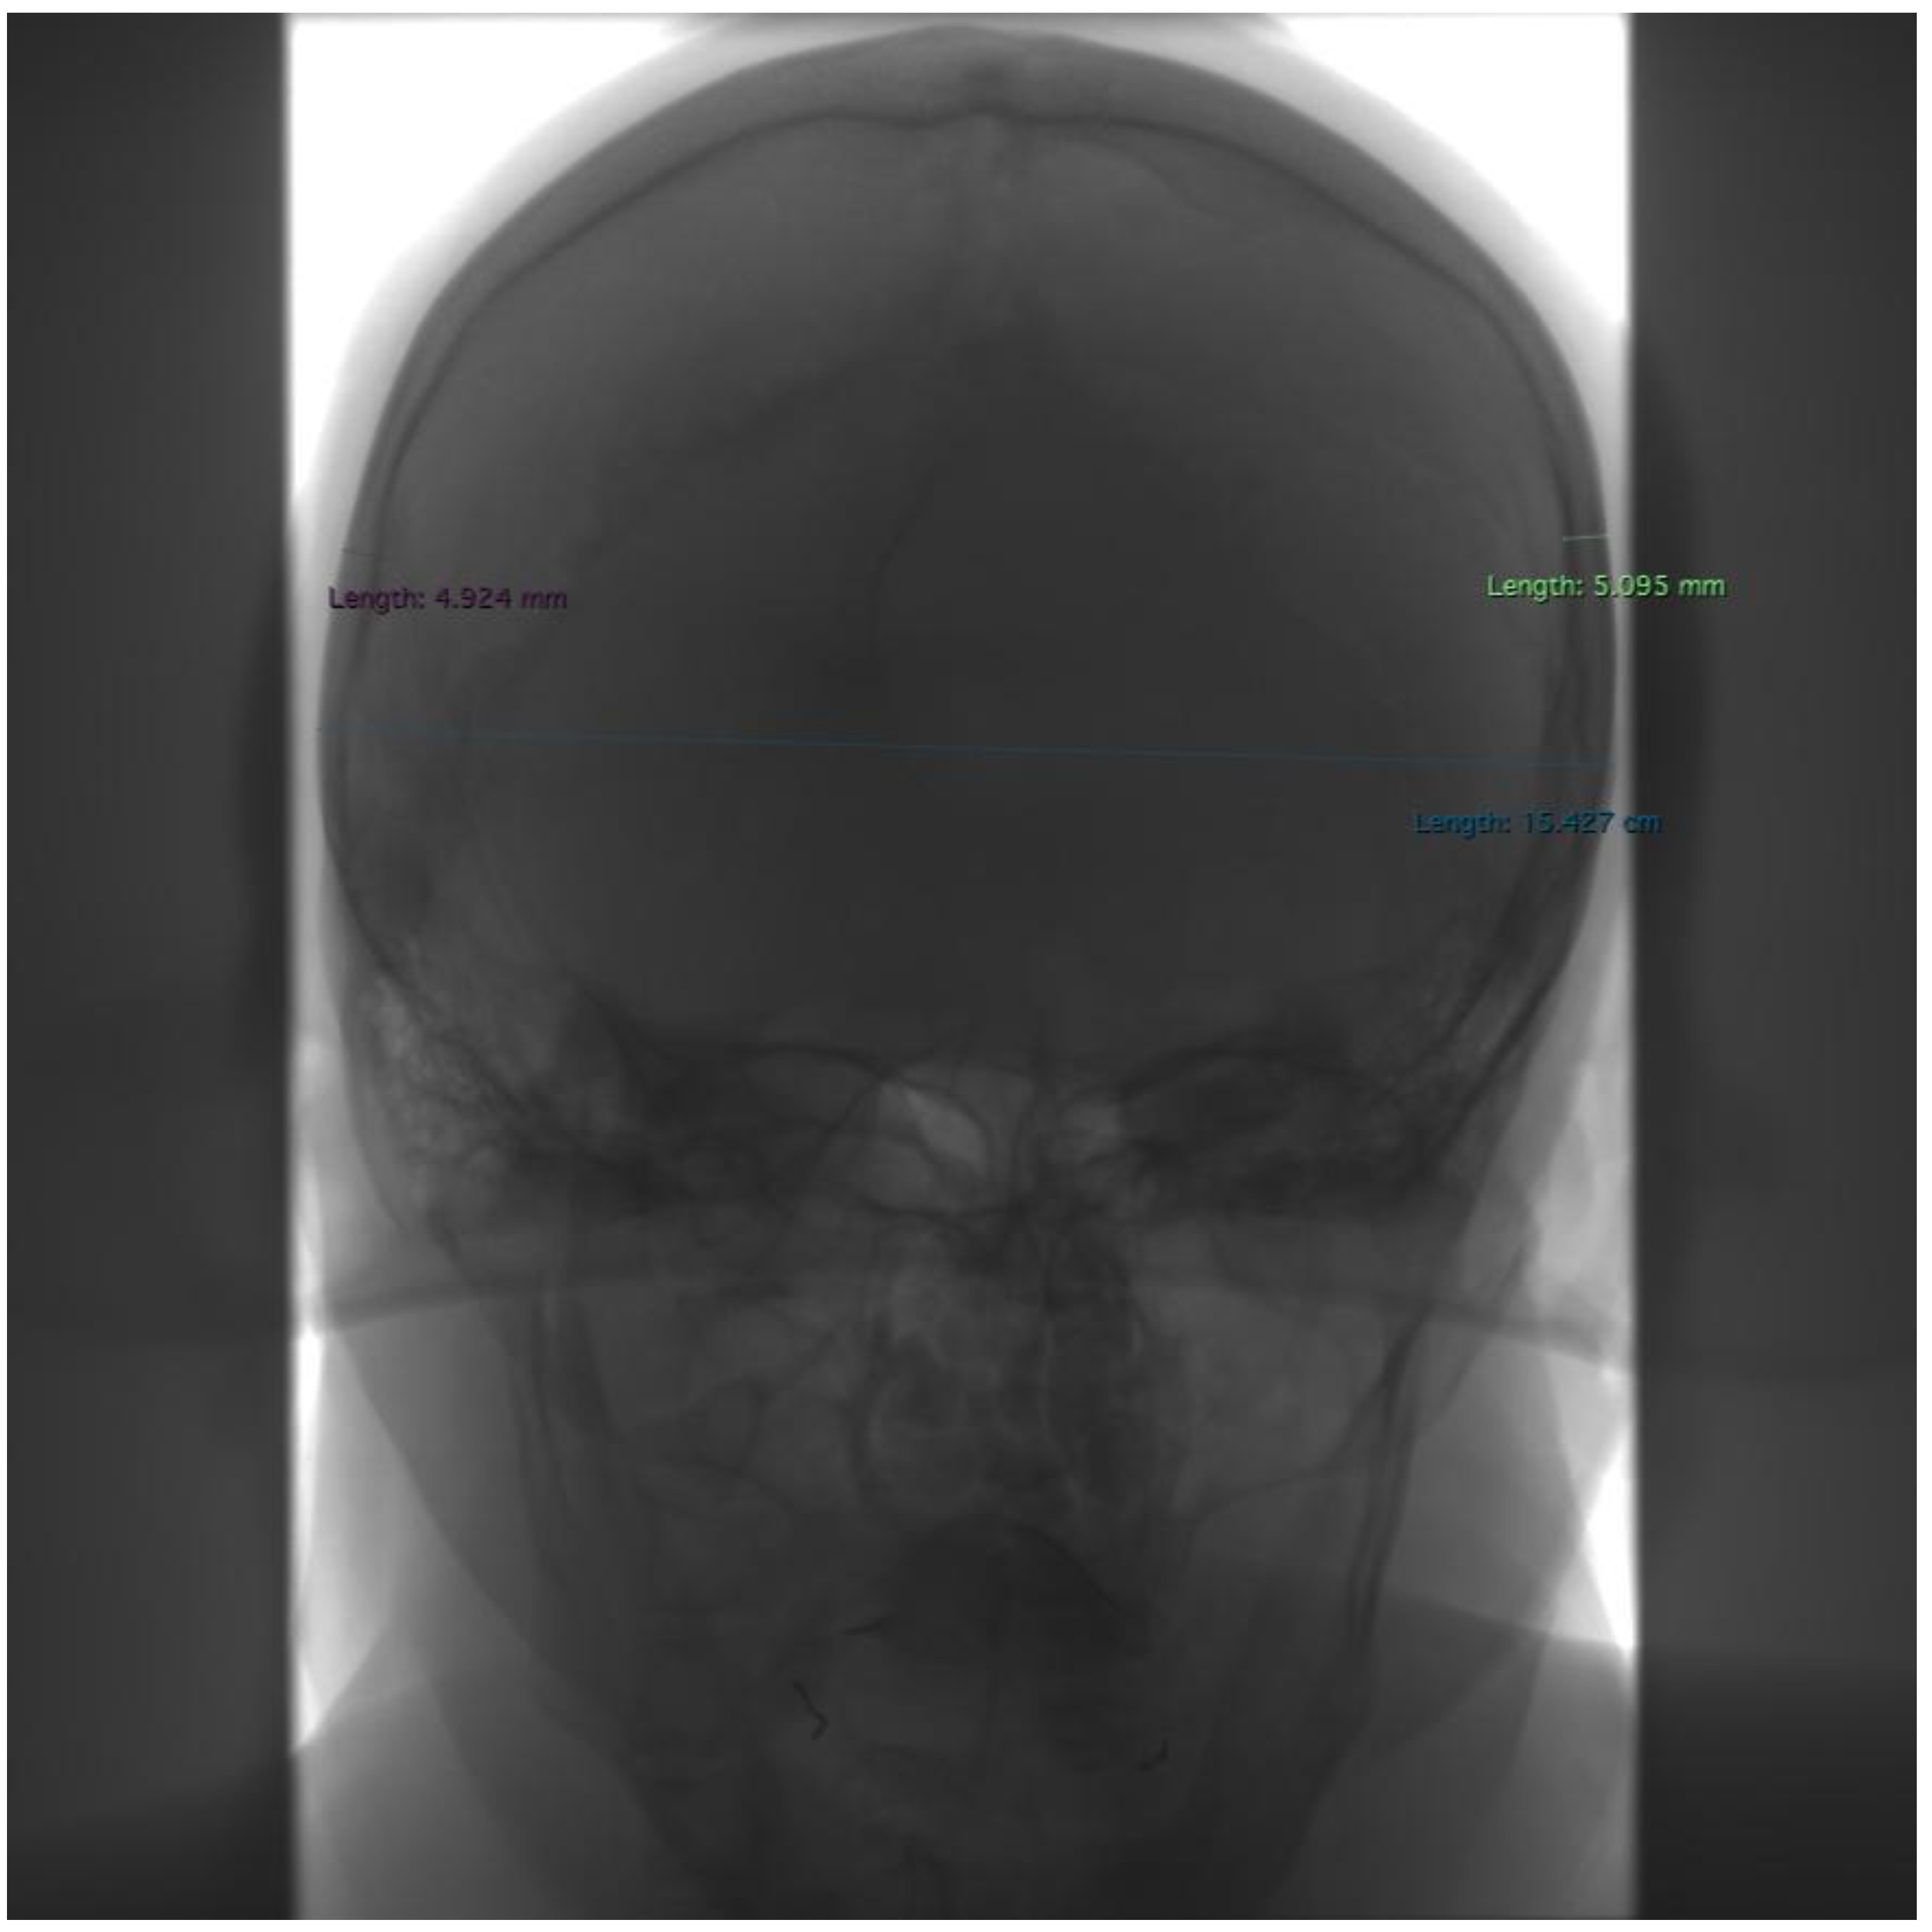

One center retrospectively analyzed medical records from a prospectively maintained database of patients who underwent DSA. All DSA examinations were performed between 31 January 2020 and 9 April 2021 in patients with suspected or confirmed central nervous system vascular aneurysms. Images were obtained using a GE Innova IGS 630 (GE HealthCare Technologies Inc., Chicago, IL, USA) C-arm biplanar angiosuite using the ARTERIOGRAPHY MO protocol. During the conducted examination, the following data were collected: gender, X-ray tube parameters (kV and mA), information about the rotation of the C-arm during the examination, the number of projections performed, information about the side of the examination (right/left/both sides), the presence or absence of metal coils (after a previous embolization procedure). Contrast injection rate, in our hospital, is typical for this exam. Value of the contrast is comparable in every data. This is the reason for why authors do not analyze these parameters. Using Horos software, cephalometric measurements were taken on radiographs in PA and lateral projections. Measurements included the widest cranial width (M8), the greatest cranial thickness near the points (eu, which is the beginning and end of the chord guided to delineate the M8 line) on both sides (Figure 1), the greatest cranial length (M1), and the greatest cranial thickness near the points (g and op, which are the beginning and end of the chord guided to delineate the M1 line) on both sides (Figure 2). A total of 251 patients (181 women, 70 men) were included. The number of unilateral DSA studies was 72 L and 64 P (136 in total). The number of bilateral DSA studies was 115. A total of 251 cephalometric measurements were taken, of which 6 parameters (M8, M1, 2× eu, op, and g) were measured in each study. The scheme of measurements is shown in Figure 1 and Figure 2. The collected data were subjected to statistical analysis using Statistica Statsoft V14.0 EN software and, in the Python environment, using the SciPy library, employing a series of statistical tests. For all analyses, the significance of results was assumed for p less than 0.05. Spearman’s rank correlation was used to analyze continuous data corresponding to successive dimensions (M8, eu, M1, g, and op) with voltage and current. The Mann–Whitney U test was used to analyze the correlation of nominal data (gender, coils) with X-ray tube parameters. Due to the presence of outliers, the dataset was cleaned by applying an interquartile cut-off to the analyzed variables. Thus, 27 records were excluded, leaving 224 measurements for the analysis of X-ray tube parameters.

Figure 2. Example of measurements taken in frontal projection. Purple—the greatest cranial thickness near the right eu point, green—the greatest cranial thickness near the left eu point, turquoise—the widest cranial width (M8).